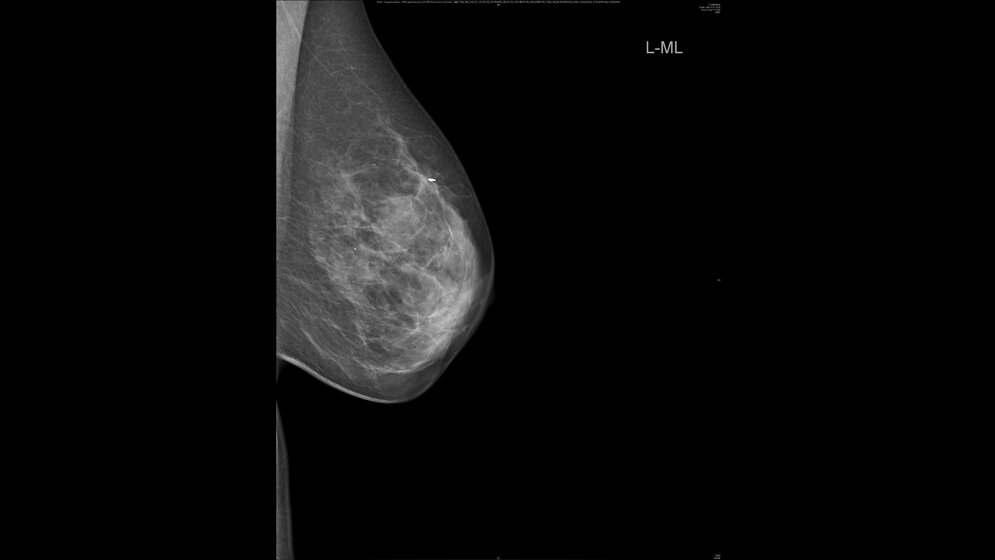

Bei rund einem Drittel der Brustkrebspatientinnen, die eine sogenannte neoadjuvante, der Operation vorgeschaltete, Chemotherapie erhalten, bildet sich der Tumor vollständig zurück, so die Uniklinik Heidelberg. Operiert werden sie bislang trotzdem, denn erst die Gewebeentnahme und -analyse bei der Operation zeige eindeutig, ob alle Krebszellen abgestorben sind. Einen Ausweg aus dieser Problematik könnte ein lernender Algorithmus bieten, der gleichzeitig mehrere Faktoren berücksichtigt. Er ermöglicht laut ersten Studienergebnissen eine zuverlässige Diagnostik, wie Wissenschaftler des Brustzentrums der Universitäts-Frauenklinik Heidelberg unter anderem mit Kollegen vom MD Anderson Cancer Center, Houston, USA, und Royal Marsen Hospital, London, Vereintes Königreich, aktuell in einem Highlight-Artikel im European Journal of Cancer berichten.

Die Frage, wie gut die Chemotherapie im Vorfeld der Operation angeschlagen hat, lässt sich – das haben aktuelle Studien gezeigt, die von den Heidelberger Wissenschaftlern federführend durchgeführt wurden – weder mit bildgebenden Untersuchungen noch mittels Biopsie zweifelsfrei beantworten. „Das Problem bei der alleinigen Biopsie ist, dass das Tumorgewebe bei Brustkrebs häufig heterogen ist und entsprechend uneinheitlich auf die Therapie anspricht“, erläutert Seniorautor Heil. „Nur weil die Gewebeprobe aus der Biopsie keine Krebszellen mehr enthält, heißt das nicht, dass der gesamte Tumor abgestorben ist.“ Eindeutige Klarheit bringt bislang erst die Untersuchung des bei der Operation entnommenen Gewebes. Die Behandlungsrichtlinie sieht daher vor, dass alle Frauen dem ursprünglichen Tumor entsprechend operiert werden. So wird Gewebe entnommen, obwohl möglicherweise gar kein Tumor mehr vorhanden ist.

Um den Frauen mit sehr gutem Ansprechen auf die Chemotherapie eine unnötige Operation zu ersparen, machten sich die Heidelberger Wissenschaftler Methoden des Maschinellen Lernens zunutze. Dabei wird ein rechnergestütztes System darauf trainiert, aus der gemeinsamen Analyse verschiedener Faktoren Zusammenhänge zu erkennen und darauf basierend eine belastbare Diagnose zu stellen. In den Algorithmus, der sich am zuverlässigsten erwies, fließen insgesamt 27 Faktoren ein, darunter unter anderem Alter der Patientinnen, Merkmale des Tumors und die Ergebnisse einer bestimmten Art der Biopsie (Vakuum-assistiert). In einer internen wie externen Überprüfung mit Patientendaten aus den verwendeten Studien übersah das System keinen verbliebenen Tumor, was für eine hohe diagnostische Sicherheit des Algorithmus spricht.